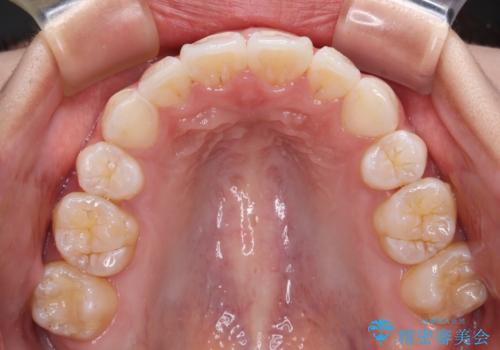

- 上下前歯の叢生を気にして来院された患者様です。

インビザラインでの治療を希望されていて、デコボコの程度が中等度であり、安価なパッケージにて対応可能と判断されたため、インビザライン・モデレートを用いて矯正治療を行うこととしました。